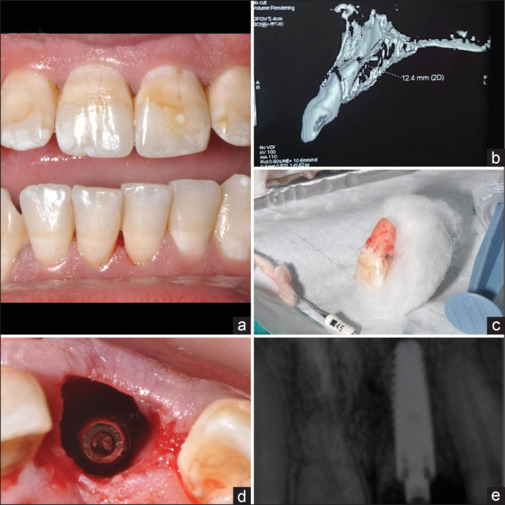

Background: Dental implants in fresh extraction sockets of the maxillary esthetic area are technique-sensitive procedures where retaining a buccal root segment can enhance periodontium preservation and esthetics. This study aims to compare marginal bone levels and esthetic outcomes between conventional immediate implant placement and the socket-shield technique in fresh maxillary extraction sockets.

Materials and methods: Twenty-four patients with type 1 extraction sockets were included in this randomized trial and assigned to either conventional immediate implant placement or the socket-shield technique. Implant survival, crestal bone levels, and pink esthetic scores (PES) were evaluated at 8 months (temporary prosthesis), 12 months, and 36 months (final crowns).

Results: All implant-supported restorations were successful within the study's observation period. The socket-shield technique showed significantly lower marginal bone loss (e.g. 1.40 ± 0.29 mm vs. 1.70 ± 0.36 mm at 36 months; P = 0.040) and superior PES (e.g., 10.50 ± 0.90 vs. 9.36 ± 0.98 at 36 months; P = 0.008) compared to the conventional technique. However, the technique's complexity underscores the need for expertise and careful execution to optimize tissue preservation in the maxillary esthetic zone.

Conclusion: The socket-shield technique better preserves hard and soft tissues around implant-retained prostheses than conventional implant placement in maxillary esthetic regions. Further studies with larger sample sizes and longer follow-up are required to validate these findings.